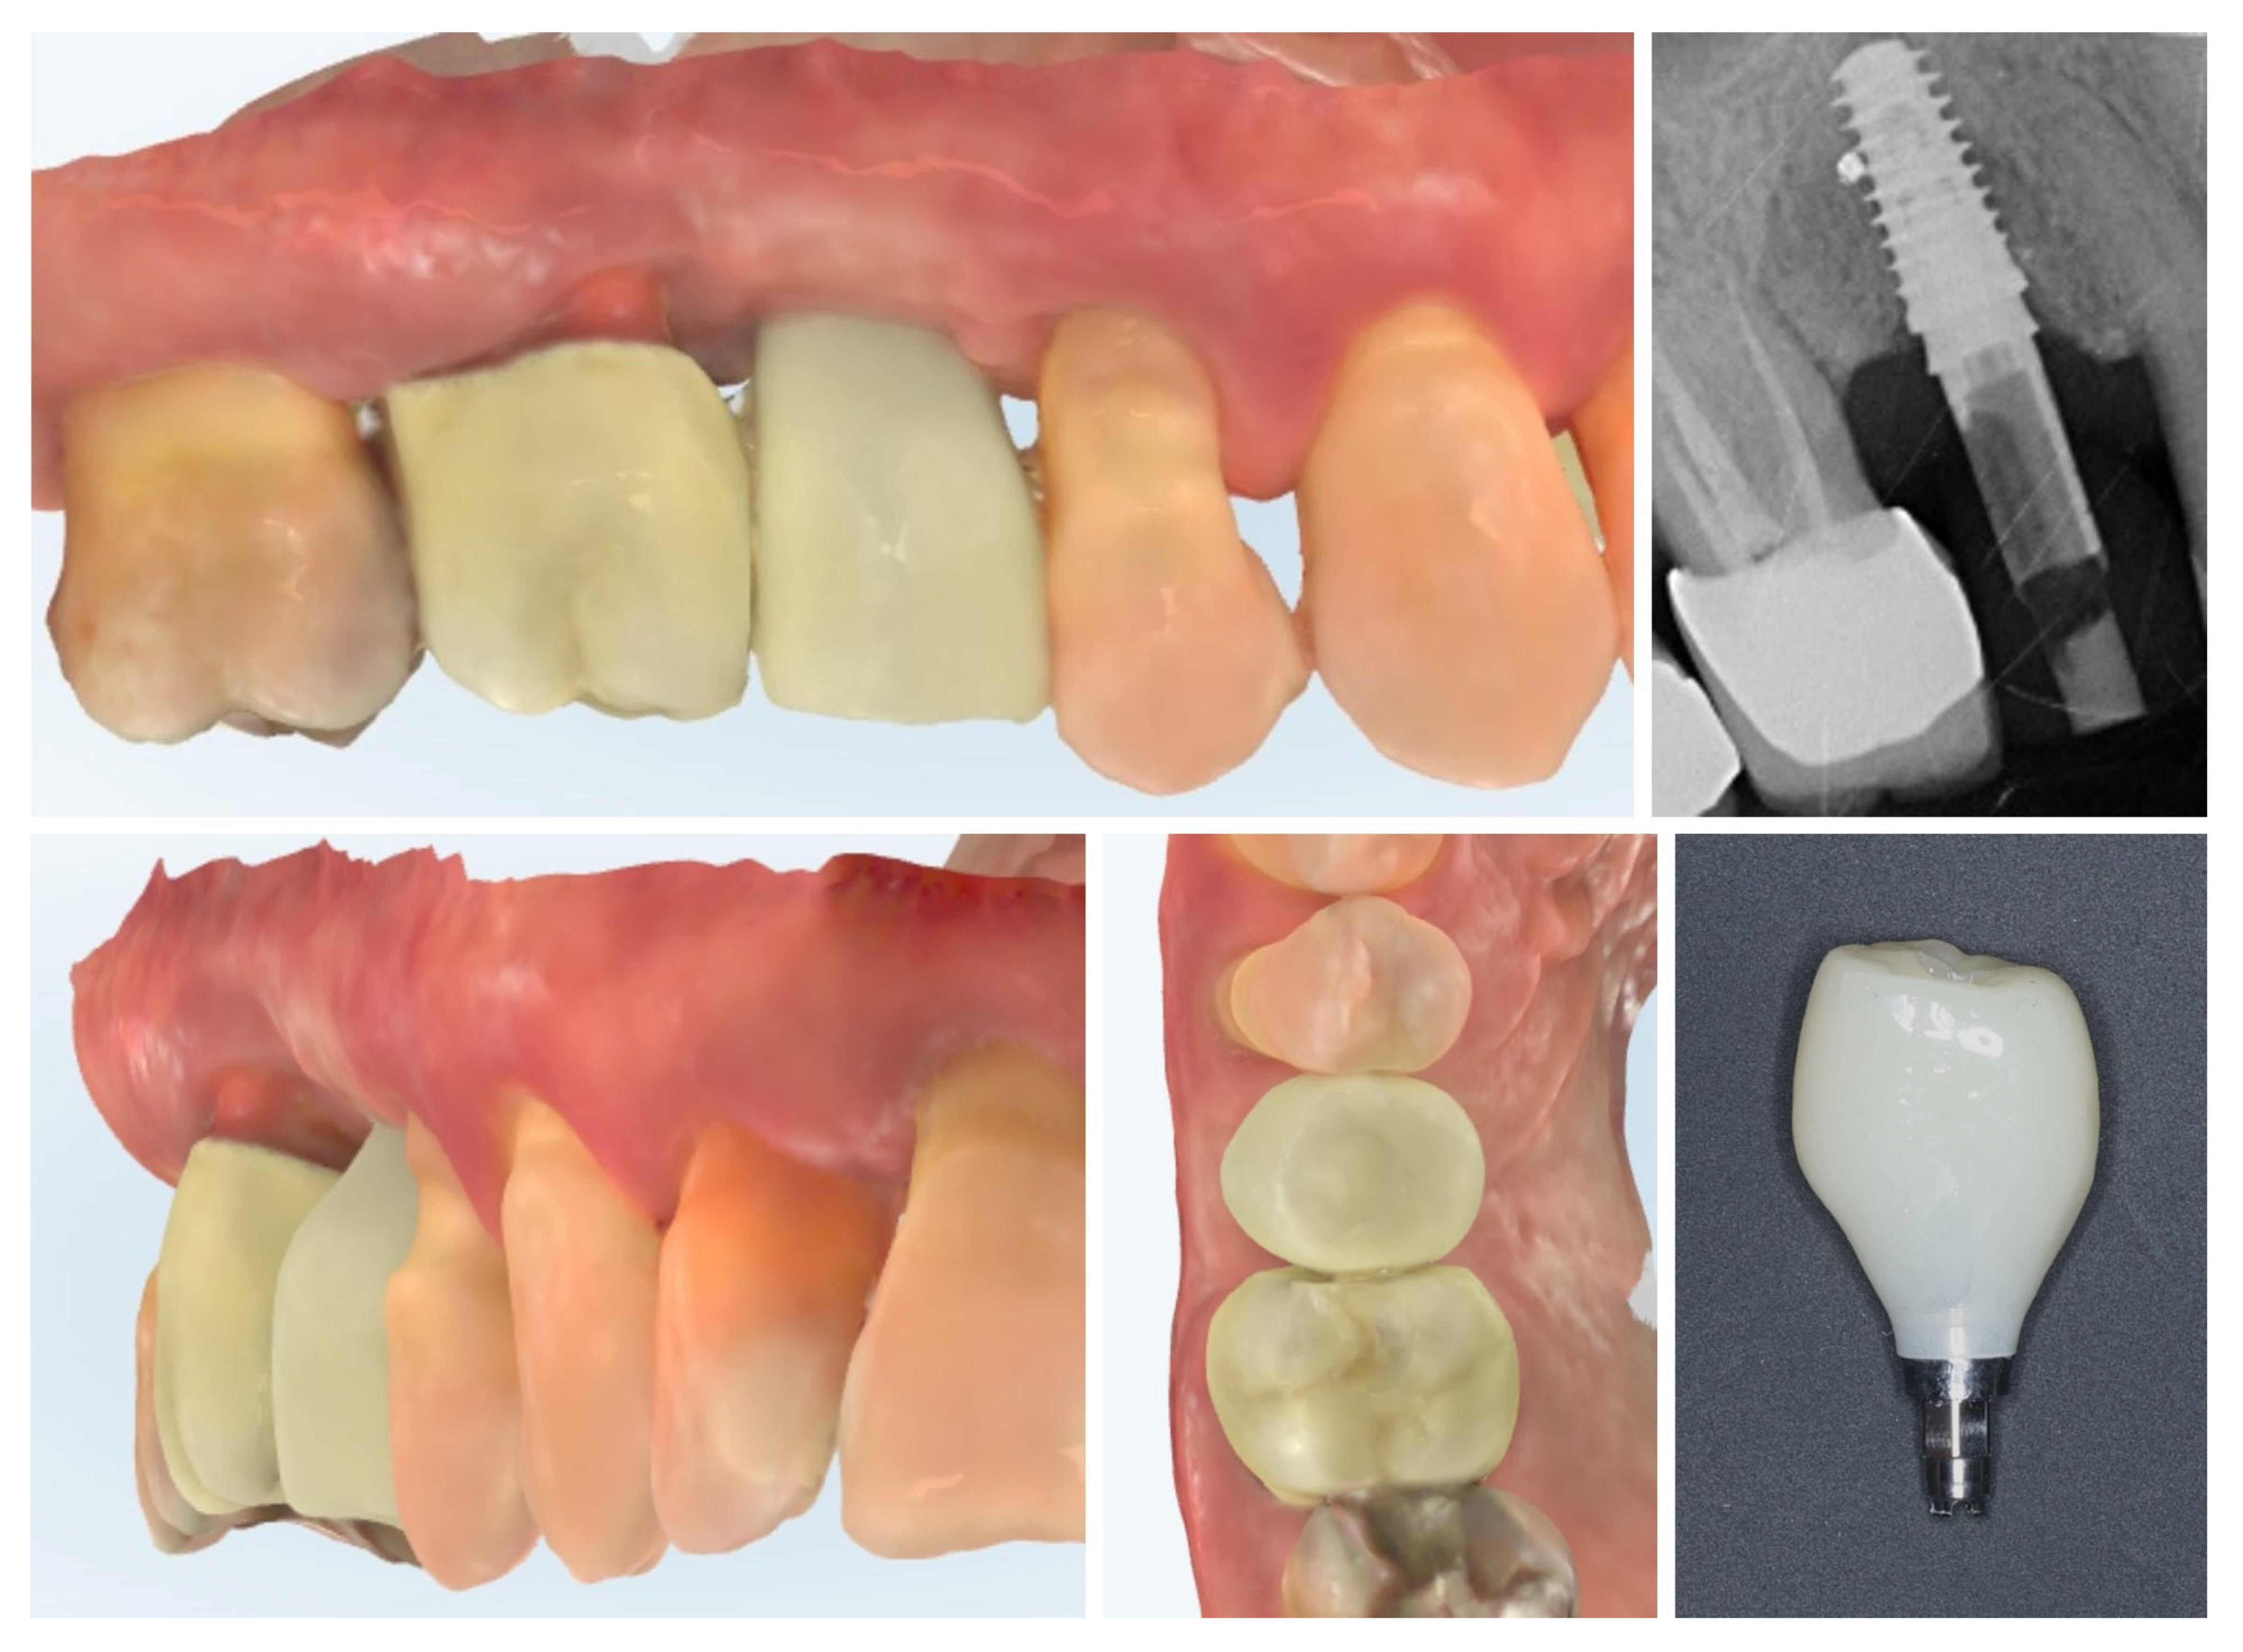

| Timepoint | Horizontal Thickness (mm) | Vertical Thickness (mm) | Clinical/Radiographic Findings | |

|---|---|---|---|---|

| 1 | Baseline (Day 0) | 2.3 | 2.4 | Initial thin buccal tissue |

| 2 | 2 weeks post-op | Uneventful healing, stable mucosal margin | ||

| 3 | 3 months post-op (with provisional) | 3.4 | 3.4 | Increased thickness, stable bone and mucosa |

| 4 | 4 months post-provisional | 3.5 | 3.6 | Stable peri-implant mucosa around provisional crown |

| 5 | 8 months post-op (final crown) | 3.5 | 4.1 | Final crown placed, harmonious soft tissue contours, and stable crestal bone |

| 6 | 14 months post-definitive | Long-term stability of soft tissue and crestal bone confirmed |